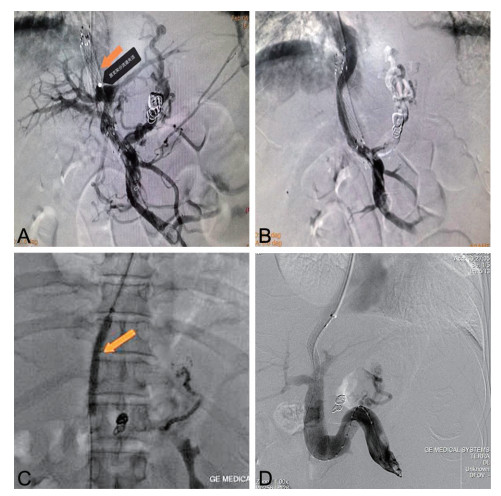

成人腹型过敏性紫癜误诊1例并文献复习

罗利绵, 李琪, 谢淼

2025, 23(7): 1262-1266. doi: 10.16766/j.cnki.issn.1674-4152.004111

443 8

摘要:

通过回顾成人腹型过敏性紫癜误诊病例,分析原因并结合临床文献资料,总结腹型过敏性紫癜疾病特点,降低误诊率。本文回顾分析了2022年7月收治的1例被误诊为急性胃肠炎的成人腹型过敏性紫癜患者的临床资料,该例患者在腹痛后期出现皮肤紫癜,同时寻求多学科会诊,更改诊断为腹型过敏性紫癜,予以糖皮质激素、抗过敏药物等对症治疗后病情好转出院。腹型过敏性紫癜少见,而成人发病率更低,因缺乏特征性临床表现及特异性辅助检查,误诊率高,临床工作者应吸取经验教训,避免误诊错治。